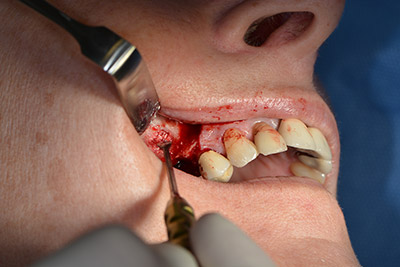

Имплантът е поставен и костта е изградена. В този случай, поради големината на зоната за аугментация, автогенните костни парченца, събрани с костен сондаж след имплантирането в зона 16 и фенестрацията в зона 14, са смесени с костозаместващ материал.

Използвана е абсорбираща мембрана като бариера на букалната страна и покритие на аугментацията. Накрая са поставени устойчиви на слюнка конци (Фиг. 15 до 19).